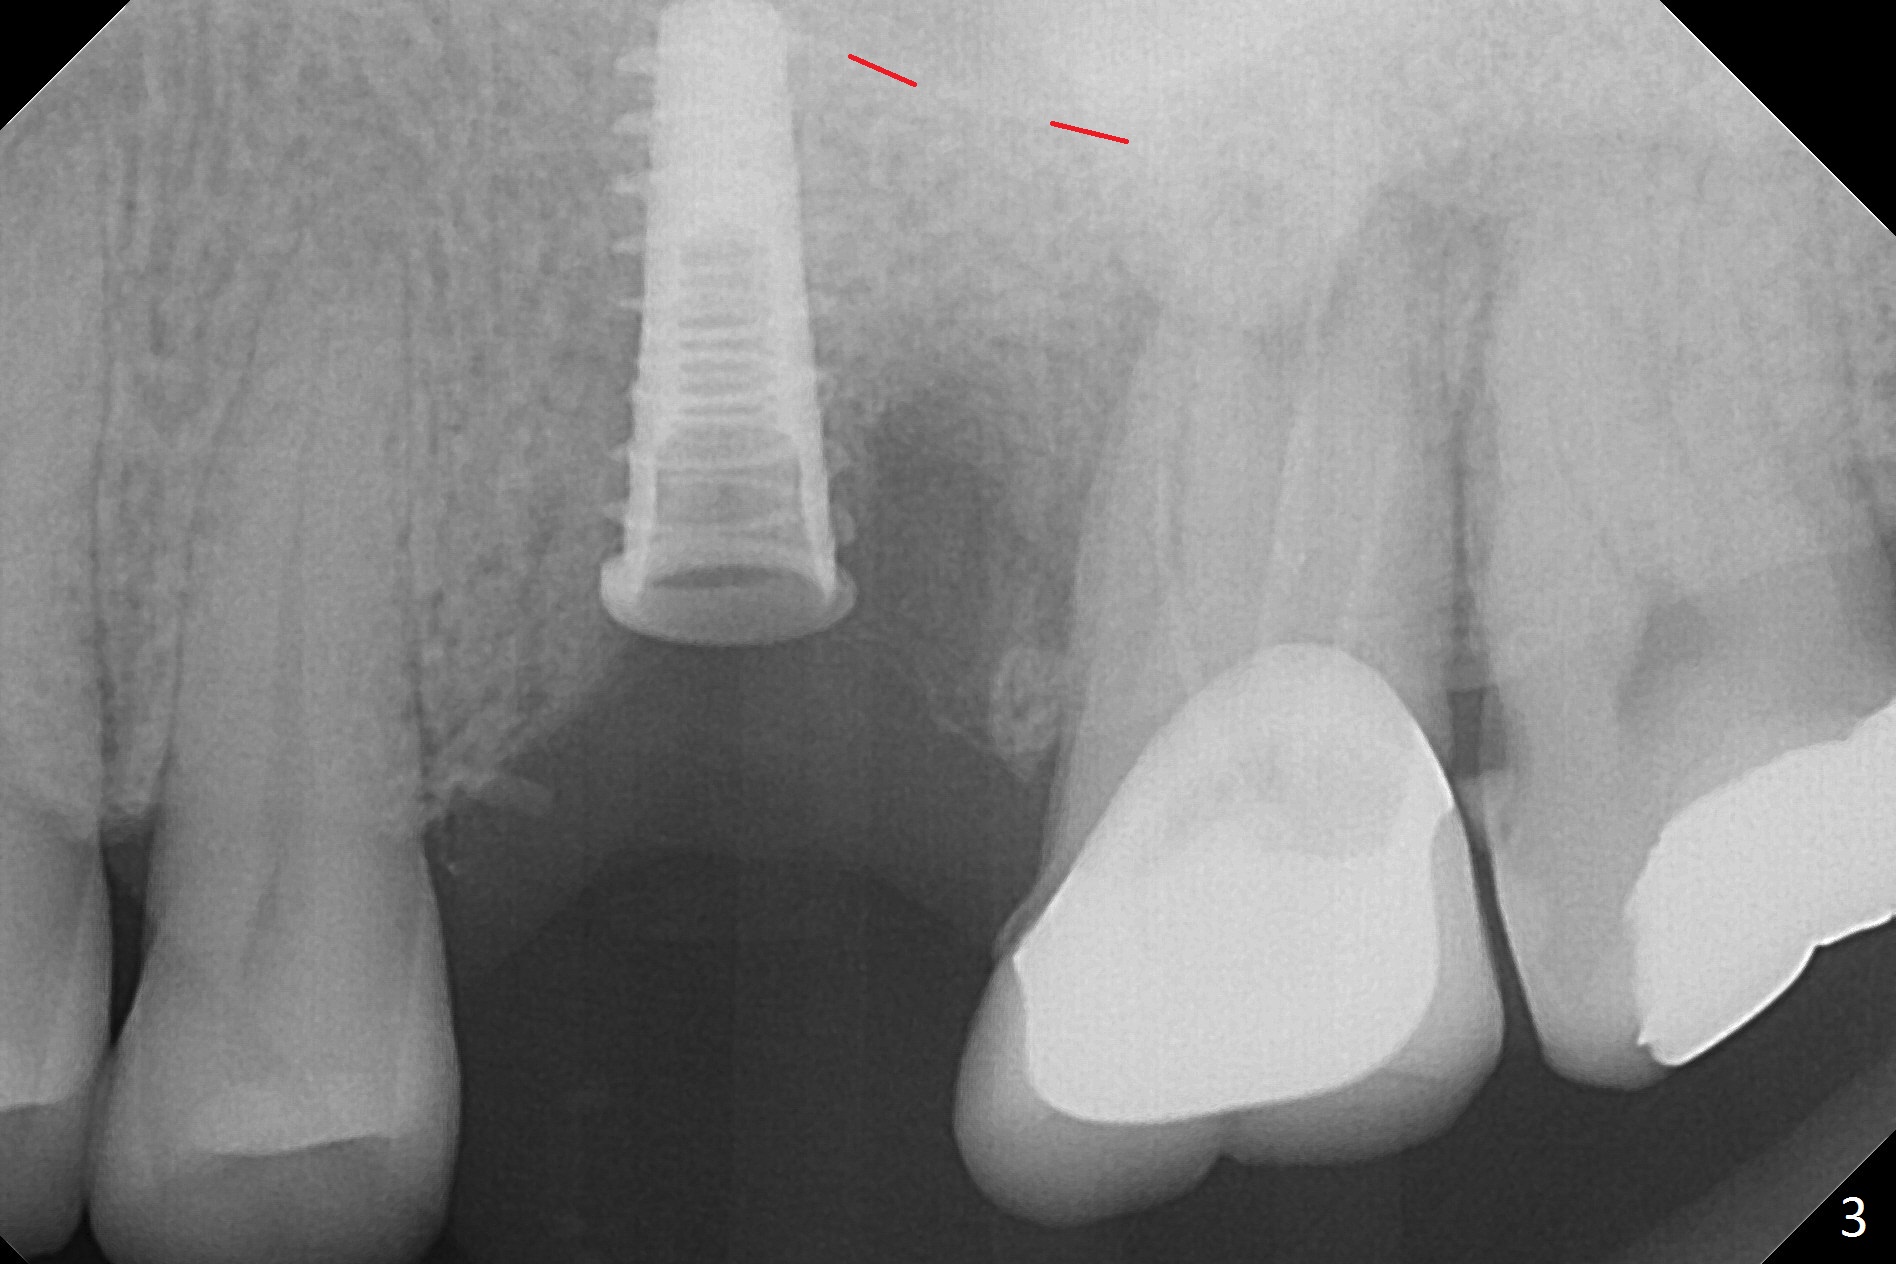

Magic Split is used to start access (flapless) and initial bone expansion at #14. The split does not go deep, since bone density is high in the deep portion. A 1.6 mm drill has to be used for 13 mm (Fig.1). Note the low bone density in the distobuccal socket (*). Later the osteotomy extends to 15 mm (gingival level). After 3.8 mm Magic Drill (MD) for 15 mm, a 4x11 mm dummy implant is placed with insertion torque of 60 Ncm (implant motor, Fig.2). After 4.3 mm MD, a 4.5x11 mm IBS implant is placed with insertion torque of 60 Ncm for implant motor >40 Ncm for torque wrench (Fig.3). The implant seems to be placed deep, but the buccal plate feels to be low. Following bone graft buccally, especially distobuccal (Fig.4,5 ^), a 5x4(3) mm abutment is placed. The buccal gingiva is torn during bone graft (Fig.6 >). Periodontal dressing is applied around the abutment (for increased retention) for wound protection.